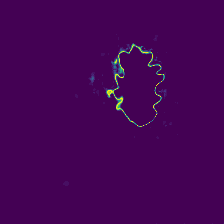

Diffusion models have shown impressive performance for generative modelling of images. In this paper, we present a novel semantic segmentation method based on diffusion models. By modifying the training and sampling scheme, we show that diffusion models can perform lesion segmentation of medical images. To generate an image specific segmentation, we train the model on the ground truth segmentation, and use the image as a prior during training and in every step during the sampling process. With the given stochastic sampling process, we can generate a distribution of segmentation masks. This property allows us to compute pixel-wise uncertainty maps of the segmentation, and allows an implicit ensemble of segmentations that increases the segmentation performance. We evaluate our method on the BRATS2020 dataset for brain tumor segmentation. Compared to state-of-the-art segmentation models, our approach yields good segmentation results and, additionally, detailed uncertainty maps.